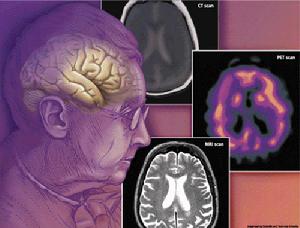

4.實驗室檢查:疑有器質性痴呆的患者應在選擇性作腰椎穿刺,血液生化檢驗,腦電圖,腦超音波,同位素腦掃描,頭顱X線平片,氣腦造影,腦血管造影或CT等檢查。